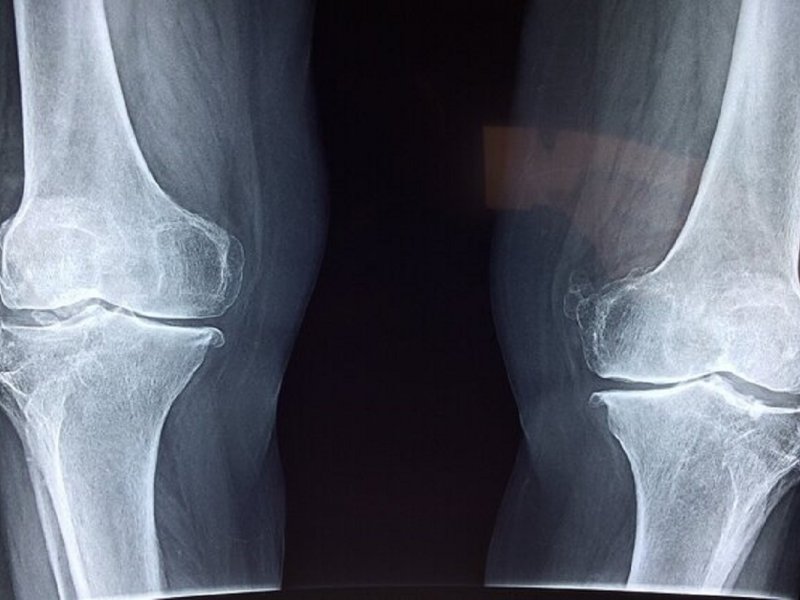

آذربانی در خصوص روشهای تشخیص بیماری توضیح داد: تشخیص پوکی استخوان با انجام سنجش تراکم استخوان (BMD) یا دگزا (DEXA) انجام میشود. این تست ساده و بدون درد، میزان تراکم مواد معدنی در استخوان را میسنجد و با کمترین میزان اشعه انجام میشود. حتی در زنان باردار نیز در شرایط خاص قابل انجام است. همه خانمهای بالای ۶۵ سال و آقایان بالای ۷۰ سال باید بدون هیچ پیششرطی این تست را انجام دهند.